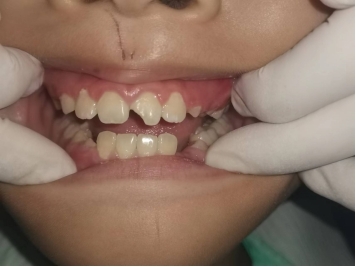

7月中旬,周末一大早7岁的赵XX随同家长着急的来到口腔科,家长说孩子昨晚上8点因车祸导致左上门牙折断并松动,折断的牙齿碎成了好几块,通过口内检查发现左上切牙切1/3缺损,好在口内没有看到露髓(牙神经)的位置,后安排拍口腔CT确诊牙根未折断,因为孩子门牙1年前才完成替换,牙根仅形成了1/2,所以及早治疗避免牙髓感染是促进孩子牙根发育的关键,周末值班患者较多,医生安排好其他患者先行给患儿进行了充填治疗,并嘱咐家长定期一定带孩子复查牙根发育情况。

这两个孩子均属于年轻恒牙外伤折断的病例,同样是左上中切牙折断,但因为年龄不同,所以他们牙根发育情况不同,通常年轻恒牙替换后后3~5年牙根才能发育完成,病例1牙根基本已发育完成,而在临床上令医生有时惋惜的是病例2这种牙根未发育完成的年轻恒牙,往往因为家长疏忽大意延误了最佳治疗时间,从而导致折断牙齿牙根发育停止甚至最终被拔除的结果。